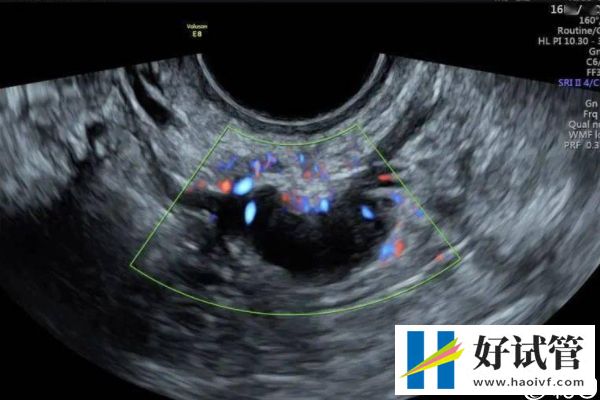

- 取卵后移植前要密切监测自己的内膜情况,相因建议各位要遵医嘱按时到医院做全面检查,如B超检查、激素水平检测等,在子宫内膜环境适宜的情况下,才可以安排胚胎移植手术。如果宫腔环境差,容易造成胚胎着床失败。